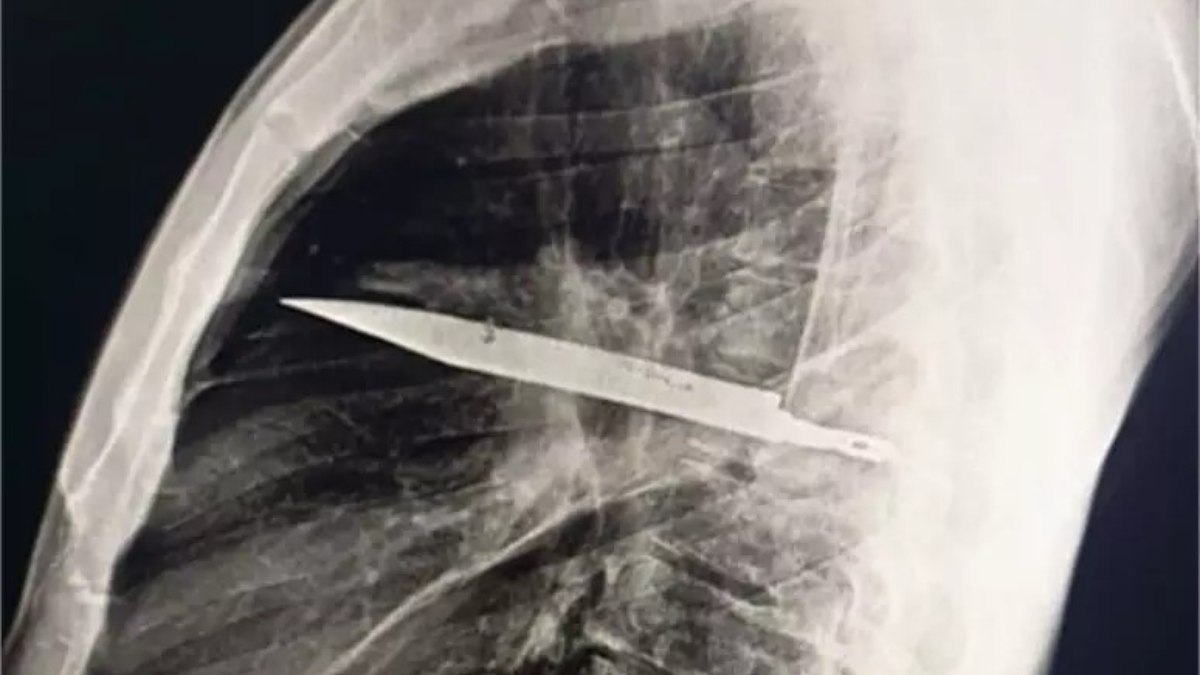

Depois do relato, o paciente passou por uma radiografia, que revelou a lâmina atravessada no tórax, sem atingir órgãos vitais.

Segundo os médicos, o acúmulo de pus foi causado pela presença do corpo estranho e por tecido danificado ao redor.